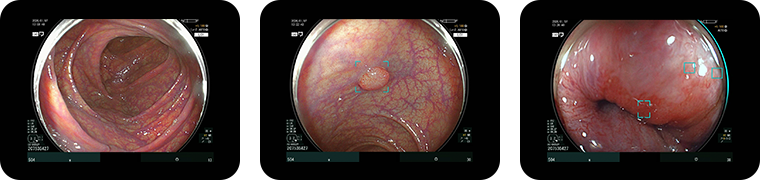

• 大腸カメラ検査の様子

• 大腸カメラ(下部消化管内視鏡検査)

大腸全体を詳細に観察

肛門からスコープを挿入し、直腸から盲腸まで大腸全体を観察します。

ポリープの発見・切除 出血源の確認 炎症性疾患の診断 大腸癌の早期発見 が可能です。

大腸カメラ検査のエコー画像